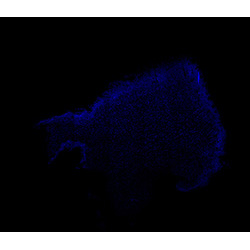

DAPI

6PCW human midbrain